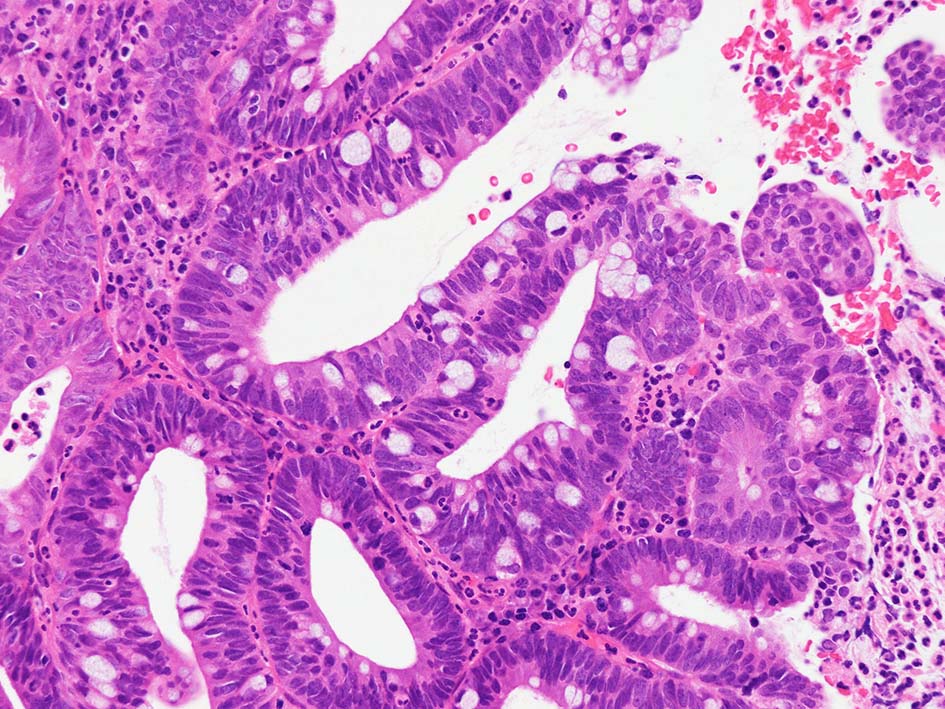

腸管型の腺癌。大腸の高分化腺癌と組織学的に区別は難しい.